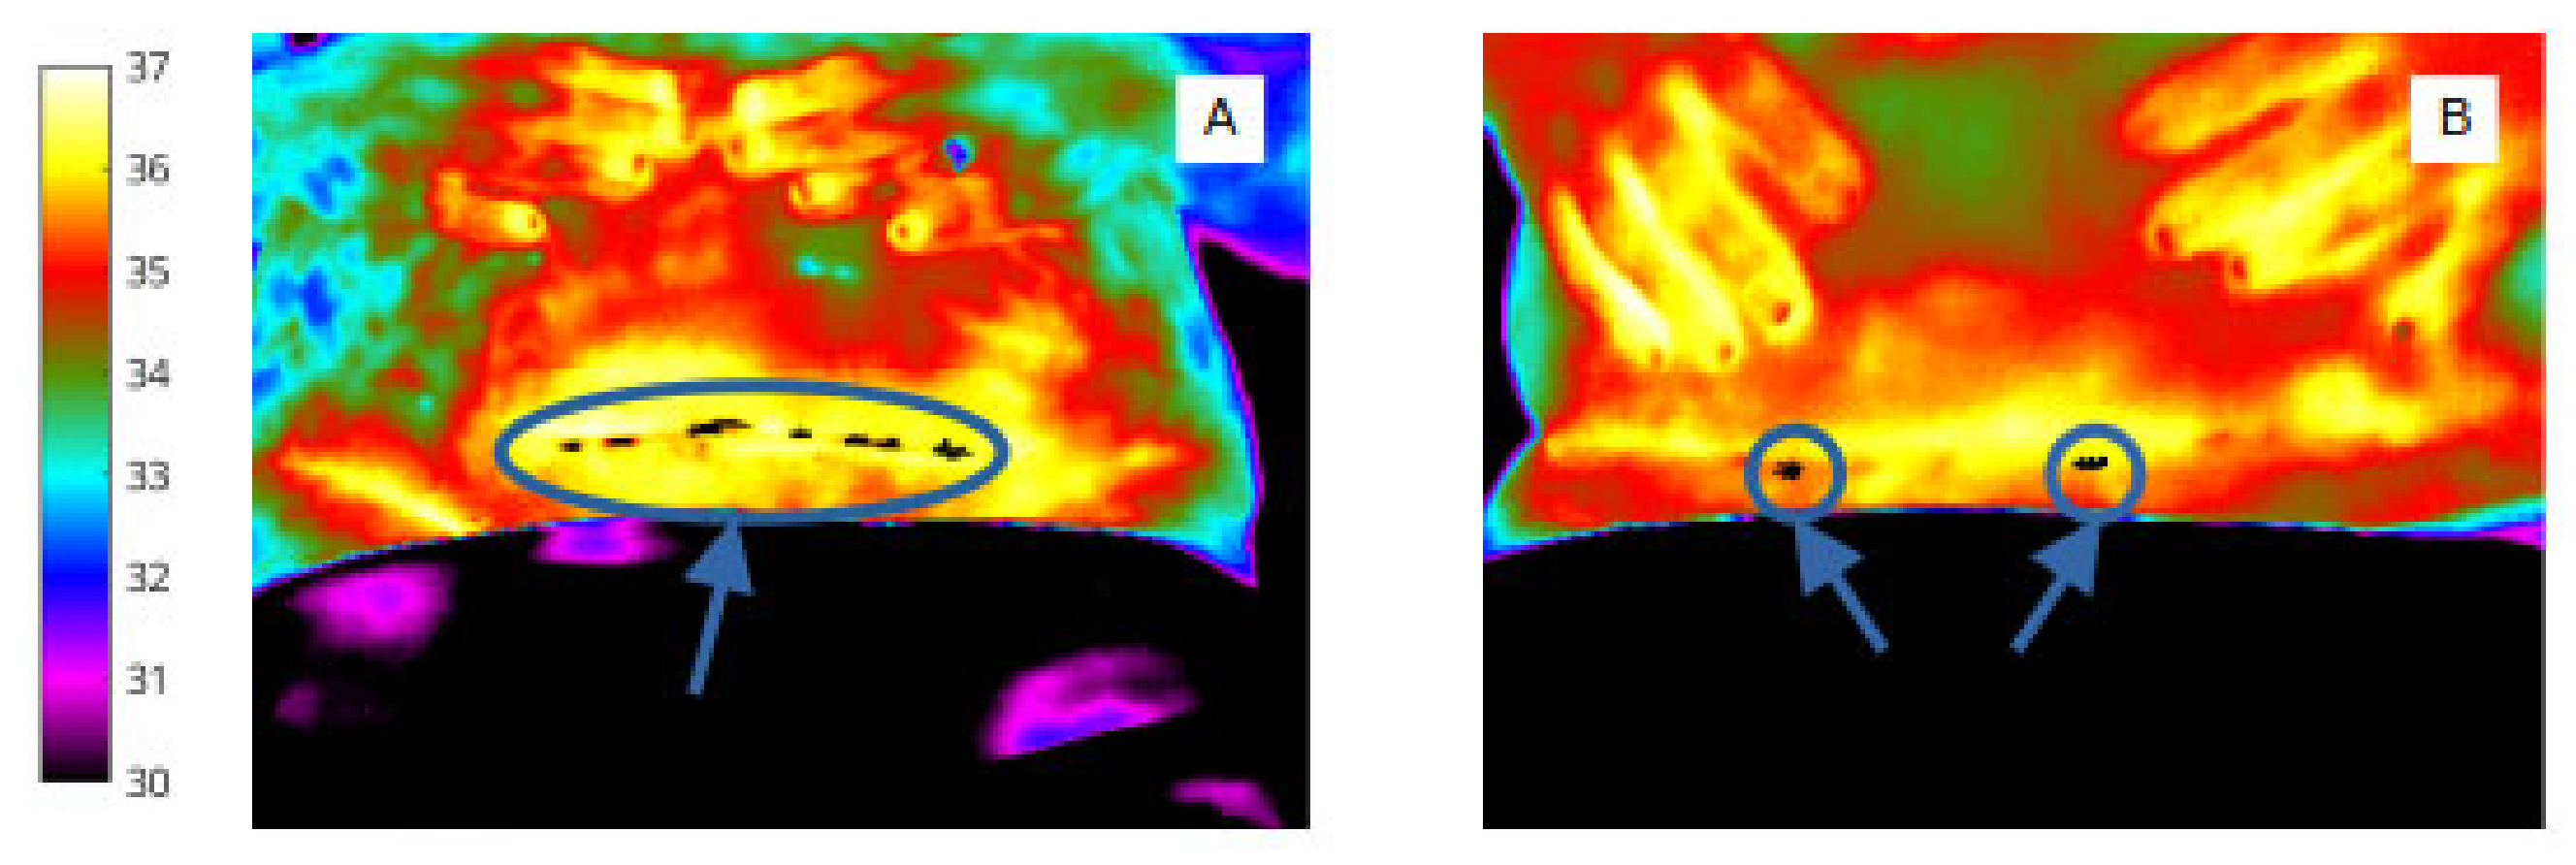

Nevertheless, it was clear from Table 2 that women who proceeded to develop an SSI had a larger number of cold spots within the wound at day 2 (by 1.07 on average) and that these cold spots covered a large area of the wound (23.92 pixels greater on average). Interestingly, the difference in number of cold spots was much lesser at day 7 (3.29 for women who developed an SSI vs. 2.79 for women who did not) and the number of cold spots was nearly the same at day 15 (2.69 for patients who developed an SSI vs. 2.39 for patients who did not). However, whilst the descriptive statistics in Table 2 indicated that the number and extent of cold spots within the wound might have predictive capability, univariate logistic regression analysis of each of these features was inconclusive for this sample size studied. An example is included here, in Figure 10.

Figure 10.

Cold spots in the wound site at day 2 of a woman who proceeded to develop SSI after caesarean section (A) and a woman with an uncomplicated wound recovery period (B).

With regard to feature extraction from within the wound area, thermal cold spots representing low temperature features were present; the pixel area of cold spots was greatest at day 2 for those who later developed SSI.